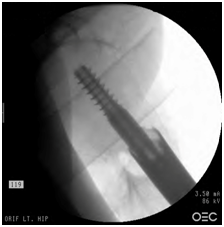

Figure 4 AP view of the left hip showing acceptable reduction and surgical fixation with an intramedullary nail.

Figure 5 Lateral view of the left hip acceptable reduction and surgical fixation with an intramedullary nail.